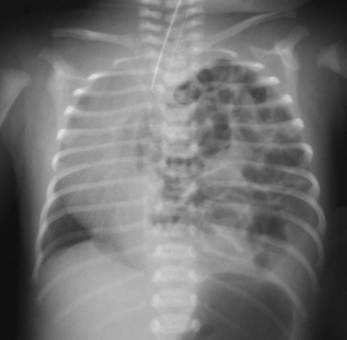

Clinical Question:

A 12-year-old male presents with recurrent, profuse nasal bleeding and right-sided nasal obstruction. Endoscopy reveals a globular, vascular mass in the right nasal cavity occupying the posterior choanae and nasopharynx. A CT scan shows anterior bowing of the posterior wall of the maxillary sinus. What is the most likely diagnosis?

Options:

- Nasopharyngeal angiofibroma

- Antrochoanal polyp

- Rhinoscleroma

- Rhinosporidiosis

Correct Answer: A) Nasopharyngeal angiofibroma